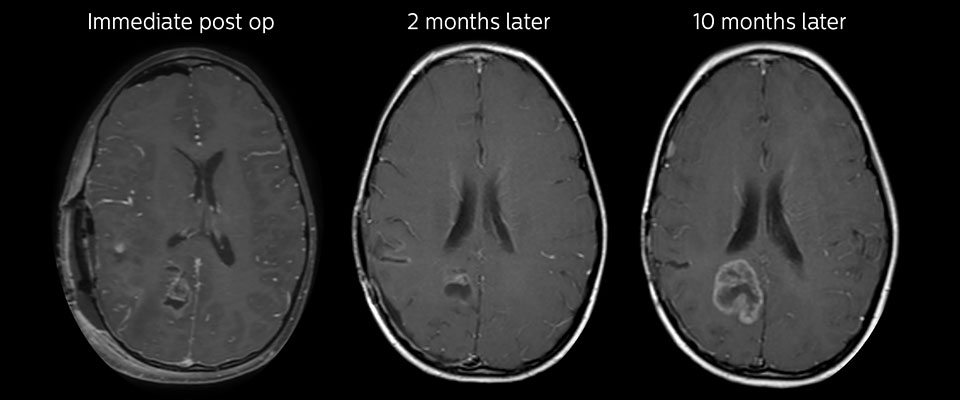

Follow-up over time

In later follow-up scans the post-contrast T1-weighted images suggest recurrent tumor growth. So, it would be interesting to study the predictive value of APT in a large patient group.